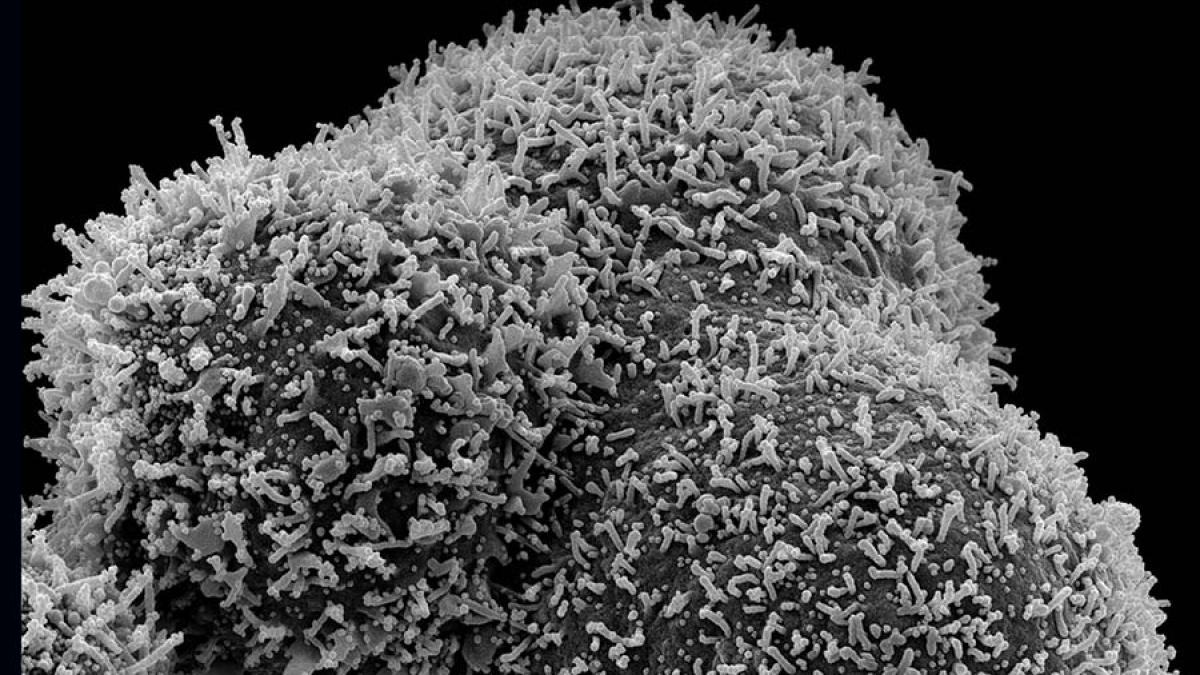

Se știe deja că există mai multe tulpini de Covid-19, lucru care are darul de a-i neliniști pe specialiști mai ales că a a început și campania de vaccinare în aproape toată lumea.

Recent medicii brazilieni au descoperit că doi pacienți au dat rezultate pozitive pentru mai mult de o tulpină de coronavirus în același timp, în ceea ce se crede că este prima infecție dublă de Covid din lume.